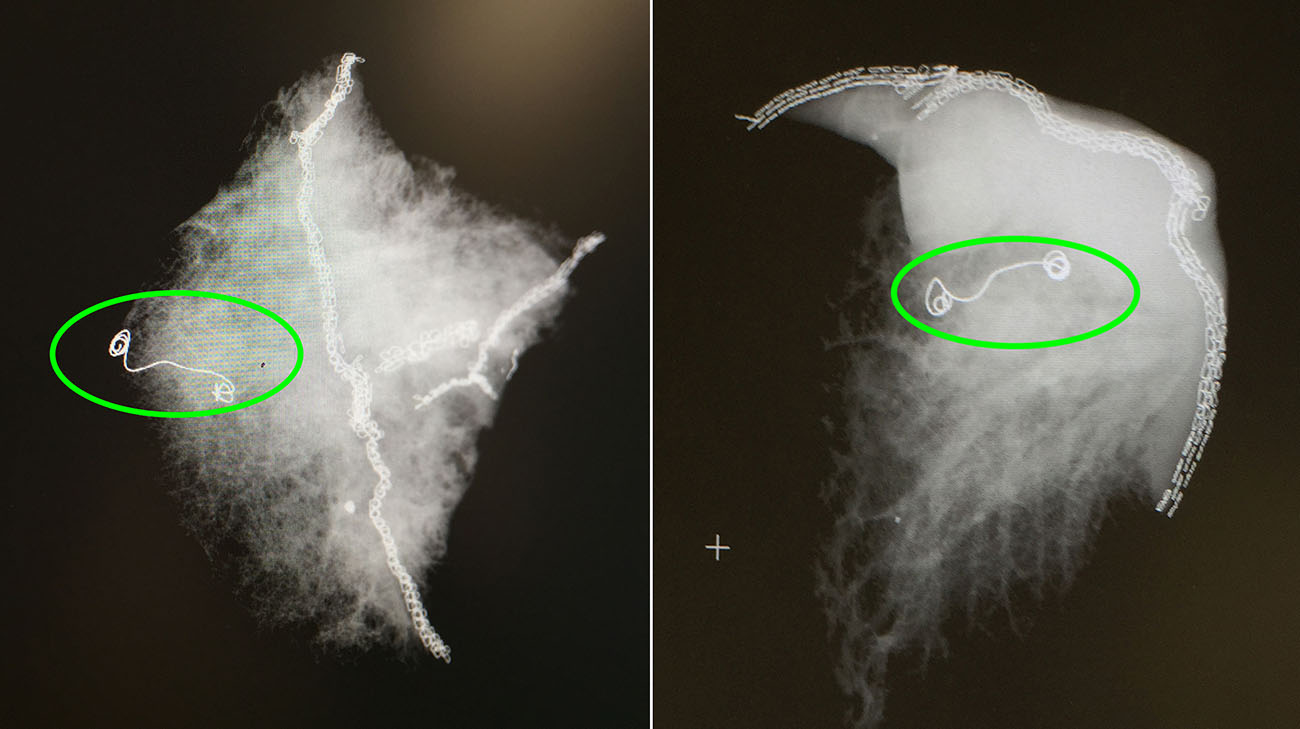

Innovative Microcoil Procedure Shows Promise For Early-Stage Lung

Innovative Microcoil Procedure Shows Promise for Early-Stage Lung my.clevelandclinic.org

microcoil lung cancer stage early procedure promise innovative shows ray cleveland clinic patient samples courtesy xray newsroom